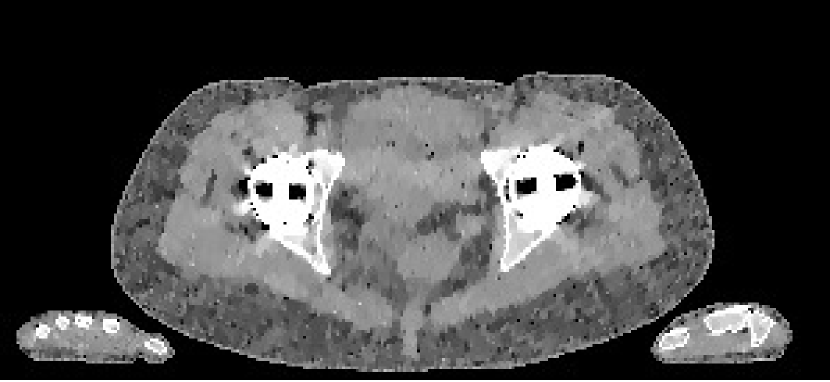

The data we used for our numerical reconstruction test were derived from the Adult Reference Computational Phantom (ICRP Publication 110,, 2009), which is a segmented image of defined density and chemical composition to represent real tissues. To investigate the ability to image metal implants, we inserted a pair of prosthetic hip joints (marked in green) with a solid titanium pin and shell. The slices through the chest and pelvis—which are the images we selected for testing—are shown in Figure 8. The resolution is 299×137299137299\times 137.

Refer to caption

(a) Chest test image

(b) Pelvis test image

Figure 8: Experimental data used: (a) is the oracle chest electron density; and (b) is the oracle pelvis electron density; both have a with display window of [0.8,1.2]